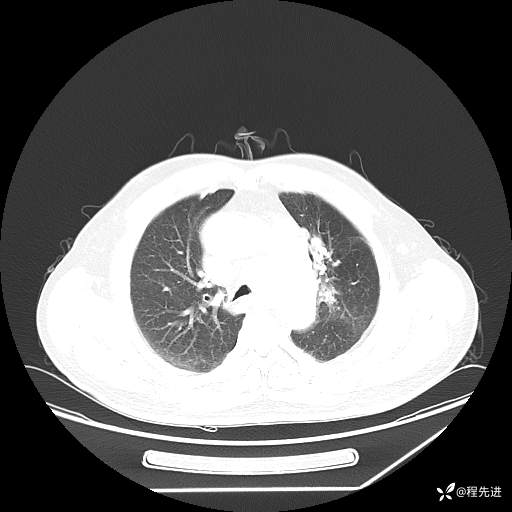

患者性别:男

患者年龄:57岁

简要病史:声嘶2月余

CT平扫+增强: